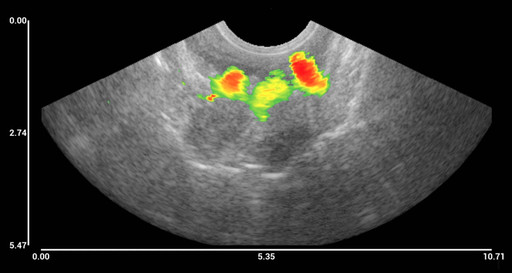

Image 1. (see image attachment) Magnetomotive ultrasound imaging of iron oxide-based nanoparticles in human tissue. Before surgery, the patient was injected with nanoparticles, and the surgical removed sample was imaged. The three coloured areas correspond to the three injection sites (1).

The scientific publication is based on extensive measurements in a laboratory environment, as well as an examination of a patient with rectal cancer undergoing rectal cancer surgery. Prior to surgery, the patient had iron oxide-based nanoparticles injected at three sites near the tumour. The patient then underwent the planned operation, and the part of the rectum where the cancerous tumour was located was removed together with the surrounding lymph nodes, according to standard clinical practice. After the procedure, the surgical removed tissue was examined with the NanoEcho prototype system, and the ultrasound image showed the nanoparticles clearly at all three injection sites.